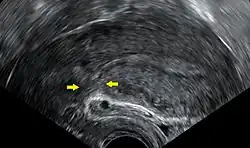

Ultrassonografia transvaginal de um útero anos após uma cesariana, mostrando a formação de cicatriz característica em sua parte anterior